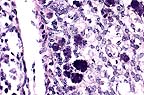

Necrotic hepatocytes in the liver of a bearded dragon. Almost every is karyomegalic as the result of a large smudgy basophilic adenoviral inclusion. (HE, 400X, 48K)

33735, unlabelled Liver, necrosis, diffuse, acute, severe with hepatomegaly and amphophilic intranuclear inclusion bodies. Stomach, intranuclear inclusion bodies, superficial epithelium, rare. Duodenum, intranuclear inclusion bodies, epithelial cells. Pancreas, intranuclear inclusion bodies, acinar cells, rare.

33733 Liver, necrosis, diffuse, acute, severe with hepatomegaly and amphophilic intranuclear inclusion bodies. Duodenum, intranuclear inclusion bodies, epithelial cells. Pancreas, intranuclear inclusion bodies, acinar cells, rare. Lung, normal.

33709 Liver, necrosis, diffuse, acute, severe with hepatomegaly and amphophilic intranuclear inclusion bodies. Intestine, intranuclear inclusion bodies, epithelial cells. Pancreas, intranuclear inclusion bodies, acinar cells, rare. Stomach, normal.

Of twenty-five animals euthanized or submitted dead for necropsy, twenty showed liver lesions; most had inclusions at other epithelial sites similar to the cases presented here. The degree of hepatic inflammation associated with the presence of intranuclear inclusions varied widely. Additional sites affected in other cases included gall bladder epithelium, oral epithelium, kidney tubular epithelium, esophageal epithelium, lung and salivary gland. Viral culture produced only contaminants. Adenovirus-like particles were observed in electron micrographs of liver tissue from several affected animals. A very similar outbreak among juvenile Rankin's dragon lizards (Pogona henrylawsoni) has been reported (Frye et al., 1994), characterized by hepatic necrosis with large, basophilic intranuclear inclusion bodies. Electron microscopy showed numerous intranuclear paracrystalline arrays of adenovirus-like particles. A similar adenovirus infection has been reported in a bearded dragon in New Zealand (Julian and Durham, 1990).

1. Liver: Necrosis, disseminated, with numerous basophilic intranuclear inclusion bodies, Inland Bearded Dragon (Acanthodraco vitticeps), reptile.

2. Stomach, duodenum, and pancreas, epithelial cells: Basophilic intranuclear inclusion bodies, small numbers.

Conference Note: Adenovirus, a double-stranded DNA virus, has been reported in numerous reptiles including Nile crocodiles, boa constrictors, rosy boas, rat snakes, Gaboon vipers, Savannah monitor lizards, Jackson's chameleon, and Rankin's dragon. All of these reptiles had intranuclear viral inclusions in the gastrointestinal tract and/or liver; most also had hepatic necrosis.